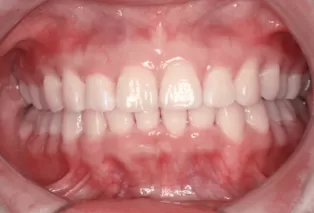

Avant le traitement

Photos intra-orales